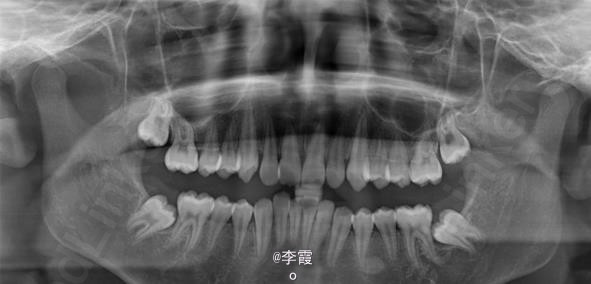

患者、马xx、15岁,主诉:牙齿不齐,要求正畸治疗。 转诊外科行下颌升支处种植体支抗直立下颌磨牙。通过患者的术前影像资料,47牙冠远中有部分骨质覆盖牙冠,采取翻瓣导萌直立磨牙。37采取电刀环切导萌直立磨牙。